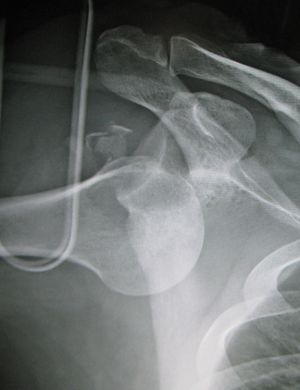

Dislocated shoulder X-ray 10.png

خلع أمامي للكتف الأيسر.

عادة ما يحدث خلع الكتف نتيجة لسقوط الشخص على ذراعه وهي ممدودة أو سقوطه على الكتف.[4] عادة ما يعتمد التشخيص على العلامات الظاهرة على الحالة ويتم التأكد عن طريق التصوير بأشعة إكس.[2] تصنف حالات خلع الكتف إلى خلع أمامي، خلفي، سفلي، وعلوي والأكثر شيوعاً هو خلع الكتف الأمامي.[2][1]

يمثل أكثر من 95% من حالات خلع الكتف، وتبرز عظمة العضد للأمام.[6] في معظم حالات خلع الكتف الأمامي، يحدث خلع الكتف عندما تصل عظمة العضد إلى مستوى الساعة أسفل ما يسمى بالناتيء الغرابي، ويشار إليه بالخلع تحت الغرابي. كما يحدث خلع تحت حقاني وتحت الترقوة، ونادراً، خلع التجويف الصدري أو خلع في تجويف خلف الصفاق.[7]